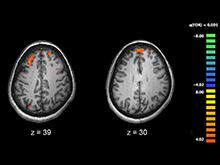

Специалисты пролили свет на роль генетики в развитии шизофрении

Университет Калифорнии обнаружил десятки генов и два биологических пути, которые могут повлиять на риск развития шизофрении. a href=http://www.upi.com/Health_News/2016/10/20/Scientists-discover-new-genetic-roots-of-schizophrenia/4391476966861>UPI.com...